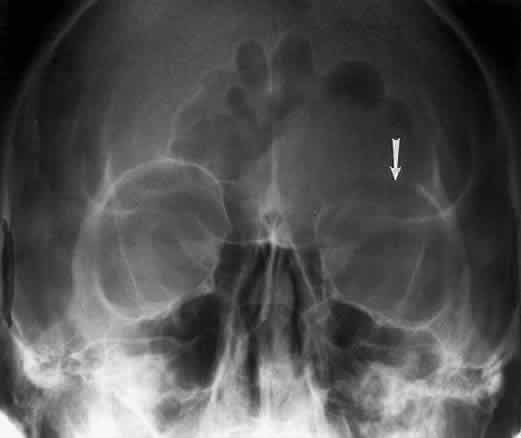

The superior orbital fissure has interpersonal and intrapersonal variations. The fissure should be symmetric, but there is no good measurement that identifies pathology, other than marked asymmetry. The fissure can be enlarged by infraclinoid aneurysm, carotid-cavernous fistulas, pituitary tumors, and meningiomas.26 Less common causes for enlargement include hemangiomas, lymphoma, mucocele of the sphenoid sinus, and neurofibromatosis (Fig. 15).

Fig. 15. Enlargement of the left superior orbital fissure (arrow) by neurofibromatosis. The Caldwell projection gives the best view of this fissure.